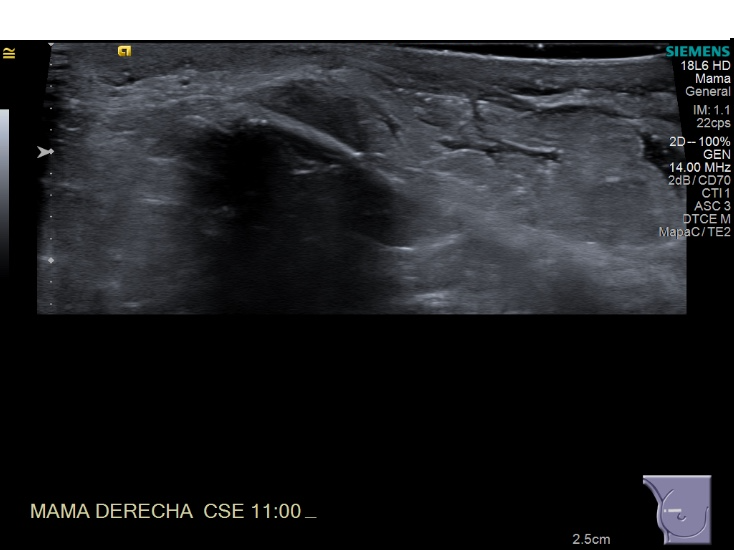

Crioablacion de tumor en mama derecha